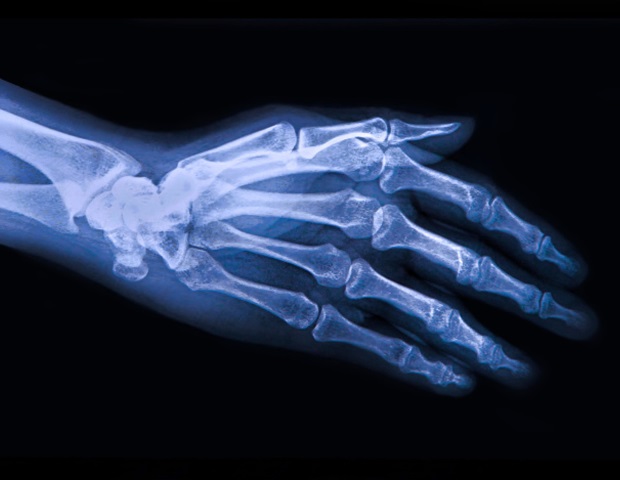

Abnutzung der Gelenke kann zu Entzündungen, Knorpelabbau und der Entstehung von Arthrose führen. Wissenschaftler der UF Scripps Biomedical Research haben ein mögliches neues Ziel zur Bekämpfung dieser schmerzhaften Kaskade gefunden.

Wenn Menschen altern und ihre Gelenke überlasten, beginnen ihre Chondrozyten zu versagen. Das Team von UF Scripps fand heraus, dass die Aktivierung eines bestimmten Proteins namens RORβ (Beta) in diesen Zellen mehrere Faktoren, die für glatte Gelenke erforderlich sind, auf ein gesünderes Niveau wiederherstellen und so zur Kontrolle von Entzündungen beitragen kann. Die Aktivierung von RORβ könnte daher eine nützliche neue Strategie darstellen, um die Entwicklung der degenerativen Gelenkerkrankung Arthrose zu verhindern oder zu verzögern, sagte Griffin, Professor für Molekularmedizin und wissenschaftlicher Direktor von UF Scripps Biomedical Research.